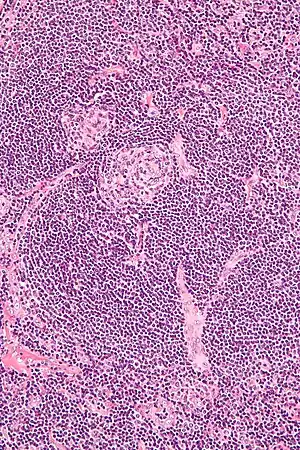

| Micrograph of Castleman disease showing hyaline vascular features including atrophic germinal center, expanded mantle zone, and a radially penetrating sclerotic blood vessel ("lollipop" sign). H&E stain. | |

- Hyaline vascular: regressed germinal centers, follicular dendritic cell prominence or dysplasia, hypervascularity in interfollicular regions, sclerotic vessels, prominent mantle zones with an "onion-skin" appearance.[14]